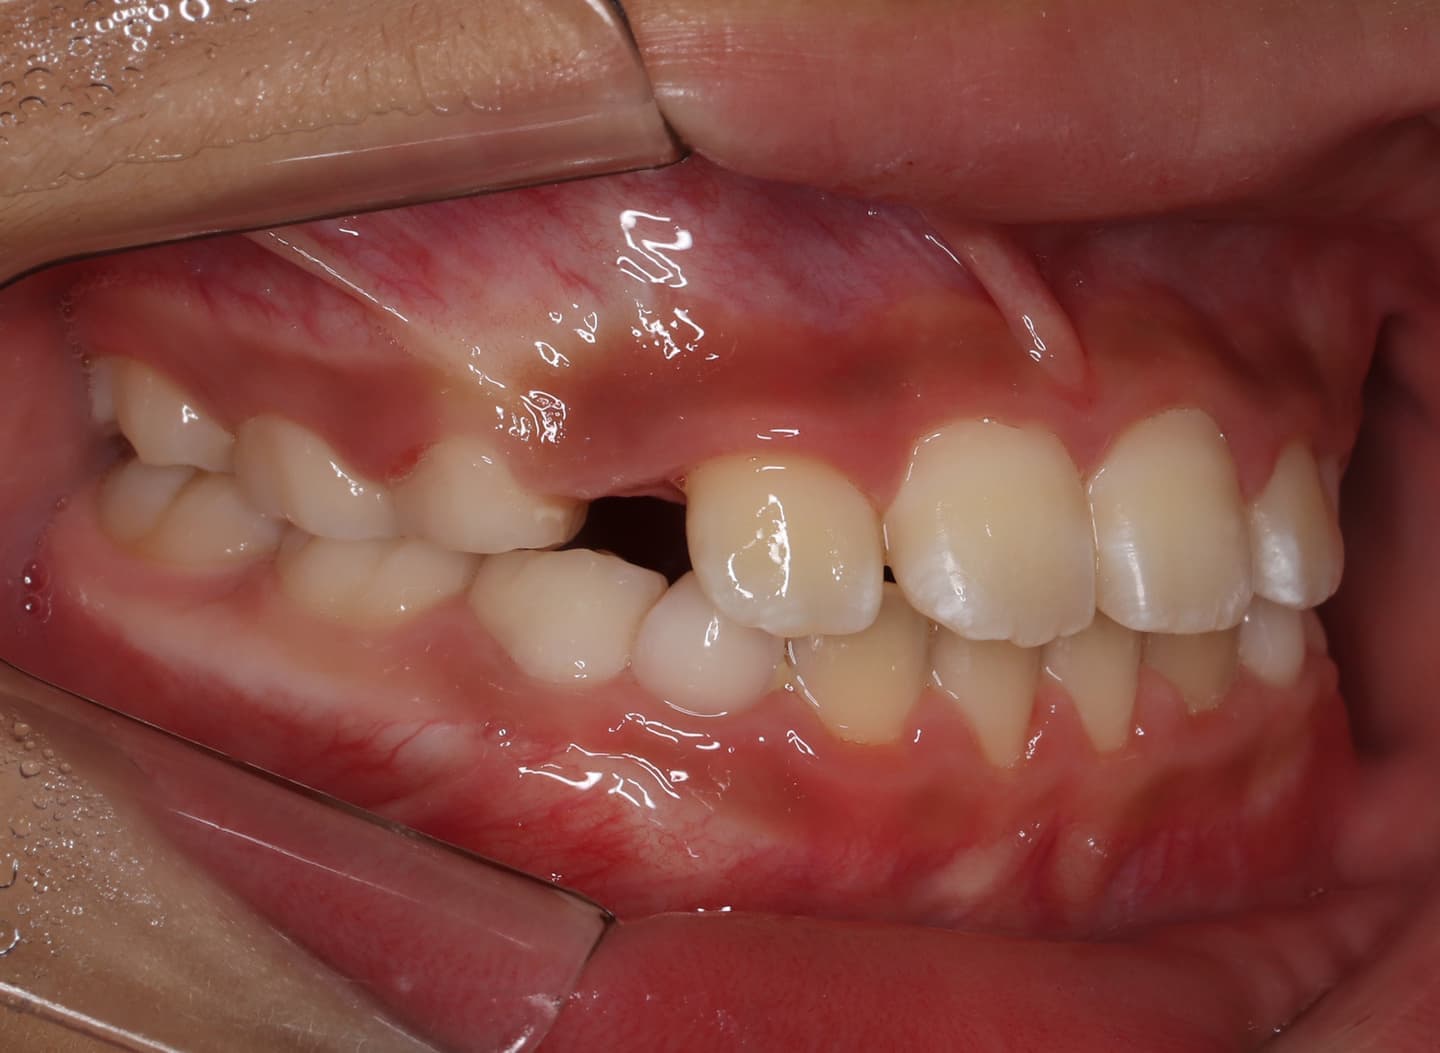

診断:初診時では右上3番の萌えるスペースがほとんどなく、顔と上顎と下顎の正中に対して、上顎前歯の正中が右にずれこんでいます。その影響で右上2番が右下乳歯Cと反対咬合になっています。放置すると、右上3番が埋伏歯になり、下顎の成長が左方向に流れるので、成長とともに顔面の非対称が増悪されることが予測されます。

右上乳犬歯が既に脱落しており、右上犬歯の萌出スペースがゼロになっています。